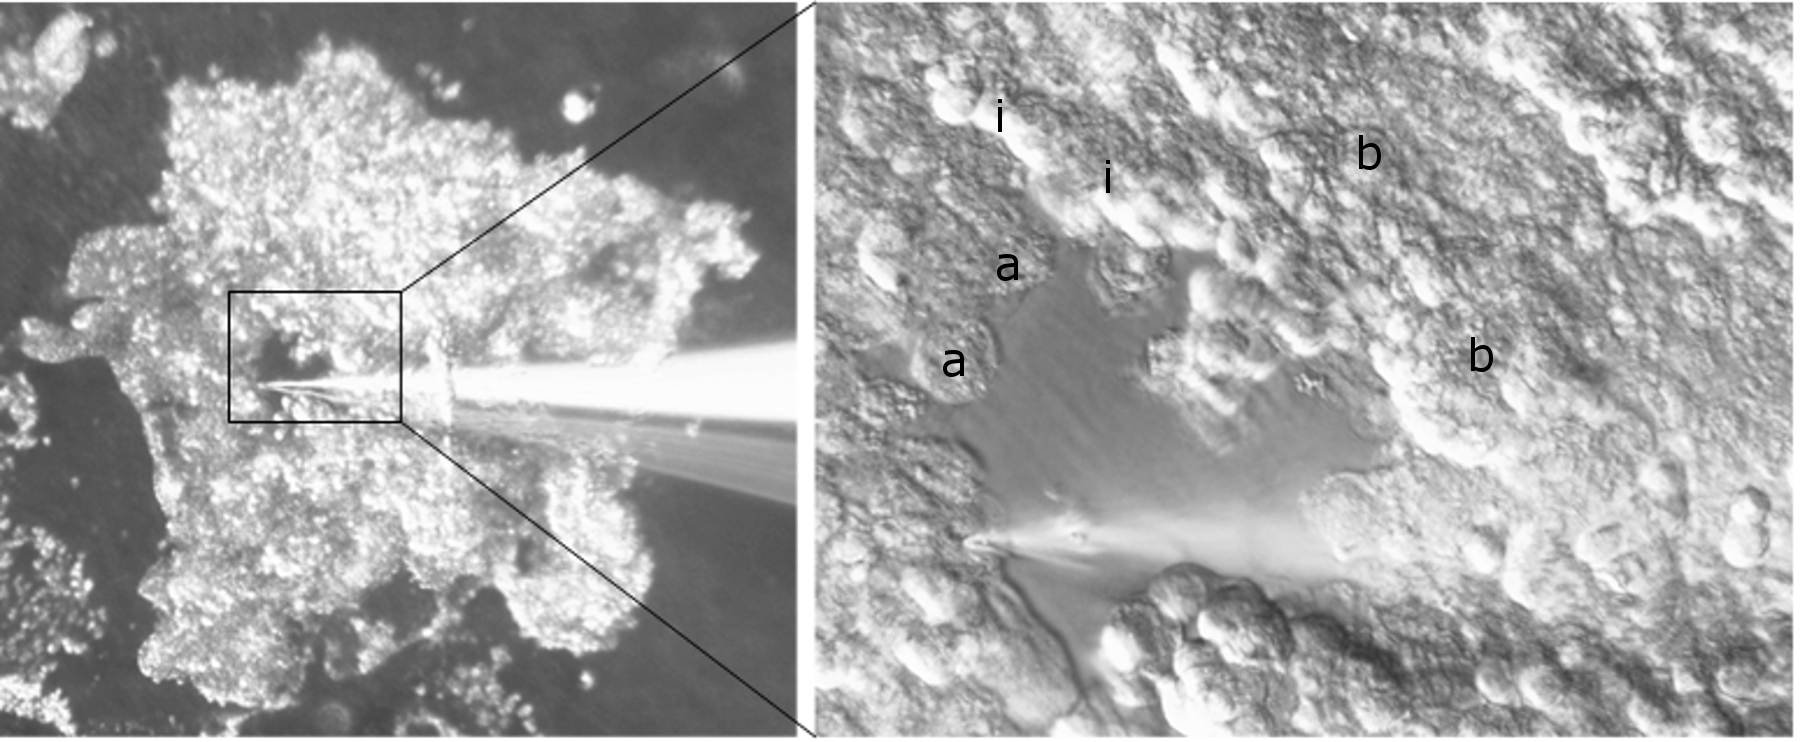

A method to study bladder urothelial cellular function in situ

Abstract 129 | HTML Downloads 66 PDF Downloads 64 Apical Cell Microdissection Downloads 0 Intermediate Cell Microdissection Downloads 0 Basal Cell Microdissection Downloads 0 | DOI https://doi.org/10.14440/bladder.2014.27Page e3